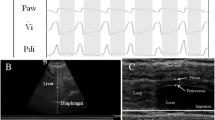

The patients were studied in the semi-recumbent position throughout the study. Ultrasonography was performed by two intensivists both experienced in ultrasonography, using an Envisor system (Philips Ultrasound, Bothell, WA) equipped with a high resolution 12 MHz ultrasound linear probe. Using the signal from the ventilator, airway pressure was displayed on the screen of the Echo-Doppler machine during NIV, ensuring accurate determination of the tracings relative to the respiratory cycle. Ultrasound recordings of diaphragm thickness were performed as previously reported [15]. Briefly, the diaphragm was located by placing the transducer in the intercostal space above the right 10th rib in the midaxillary or anteroaxillary line and directing the ultrasound beam perpendicular to the diaphragm (Fig. 1a). The zone of apposition was assessed at 0.5–2 cm below the costophrenic sinus. The inferior border of the costophrenic sinus was identified at end-inspiration as the zone of transition from the artefactual representation of normal lung (the lung sliding) to the visualization of diaphragm and liver. The diaphragm thickness was recorded in time motion (TM) mode. The sweep speed was adjusted as slow as possible to obtain a minimum of three cycles on the same image. The diaphragm was outlined by the two clear bright parallel lines of the pleural and peritoneal membranes (Fig. 1b and Online Videos). Several images were recorded and images were deemed invalid if the two clear bright parallel lines of the pleural and peritoneal membranes were not plainly identified at each moment of the respiratory cycle. Ultrasonographic recordings were stored on compact disks, and a subsequent computer-assisted quantitative analysis was performed by a trained investigator who was unaware of the ventilatory condition. The measurements included diaphragm thickness at end-expiration (T EE) and at end-inspiration (T EI). When airway pressure could not be displayed on the screen of the Echo-Doppler machine to match the ultrasound tracings to the respiratory cycle (during SB), T EE was measured just before the thickening start and T EI was measured at maximal thickening. Measurements were averaged out of three or more consecutive breaths on the last valid image recorded at the end of each period. The thickening fraction (TF) was calculated as (T EI − T EE)/T EE and expressed as a percentage (Fig. 1c).

Probe placement to explore the diaphragm in the zone of apposition (a), with the ultrasonographic view of the normal diaphragm in the zone of apposition (b) and illustration of the measurement of diaphragm thickness at end-inspiration and end-expiration in TM mode (c). T EI thickness at end-inspiration, T EE thickness at end-expiration